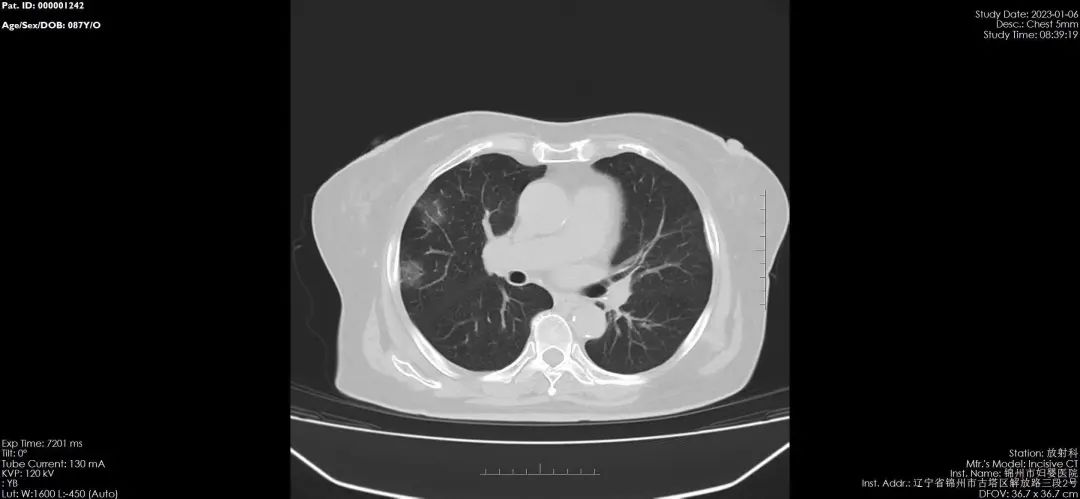

01-132023鉴于新冠病毒感染后容易出现肺部感染和肺部炎症等情况,很多感染者有肺CT检查的需求,为了让患者得到及时的检查,锦州市妇婴医院(妇幼保健院)积极开展成人及儿童的肺CT检查诊疗服务,并推出门诊优...

01-132023锦州市妇婴医院(妇幼保健院)放射线科,于2020年引进国内最新进口飞利浦64排128层螺旋CT,扫描速度快、分辨率高、层数更薄,对病毒性肺炎有着更高的检出率和准确率,可以更好的与其他肺炎进行区分,对早...